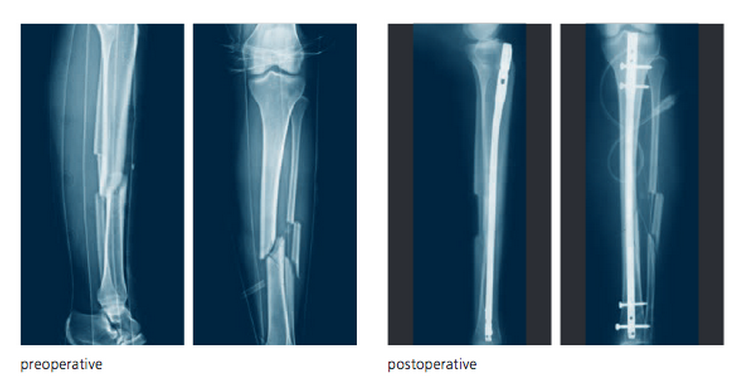

Ok, mais les blessures auxquelles je pensais sont bien des fractures telles que le pekin moyen l'entend, comme https://s3.amazonaws...12-14-26-01.png ou https://chrisgearyortho.files.wordpress.com/2017/10/fullsizeoutput_8012.jpeg. Et j'ai pas souvenir d'avoir vu beaucoup de ce type de blessure en NBA avant les 4-5 dernieres annees ?

Les fractures que tu nous montres ne sont pas vraiment des fractures de fatigue...